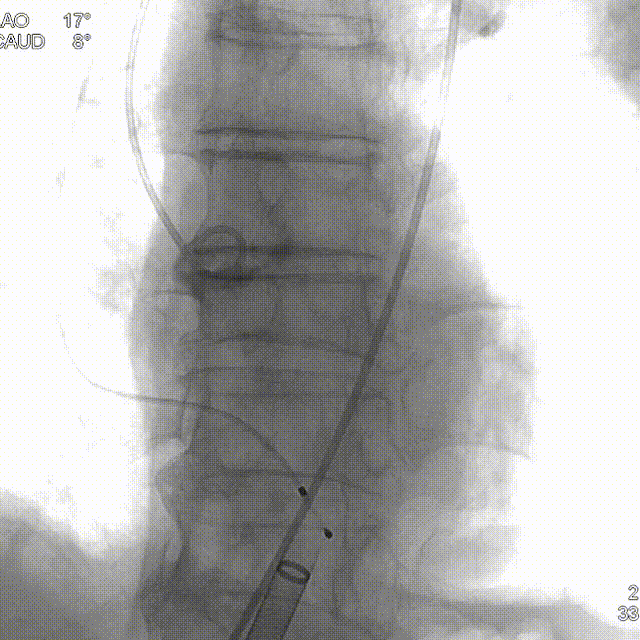

• 跨瓣角度为LAO 17° CAU 8°(右窦中心位)左右,使用22mm球囊预扩张,球囊预扩角度为LAO 17° CAU 8° (右窦中心位)左右;

主动脉根部造影,少量反流,采用22mm球囊预扩,轻微腰征,造影微量瓣周漏。

球囊预扩